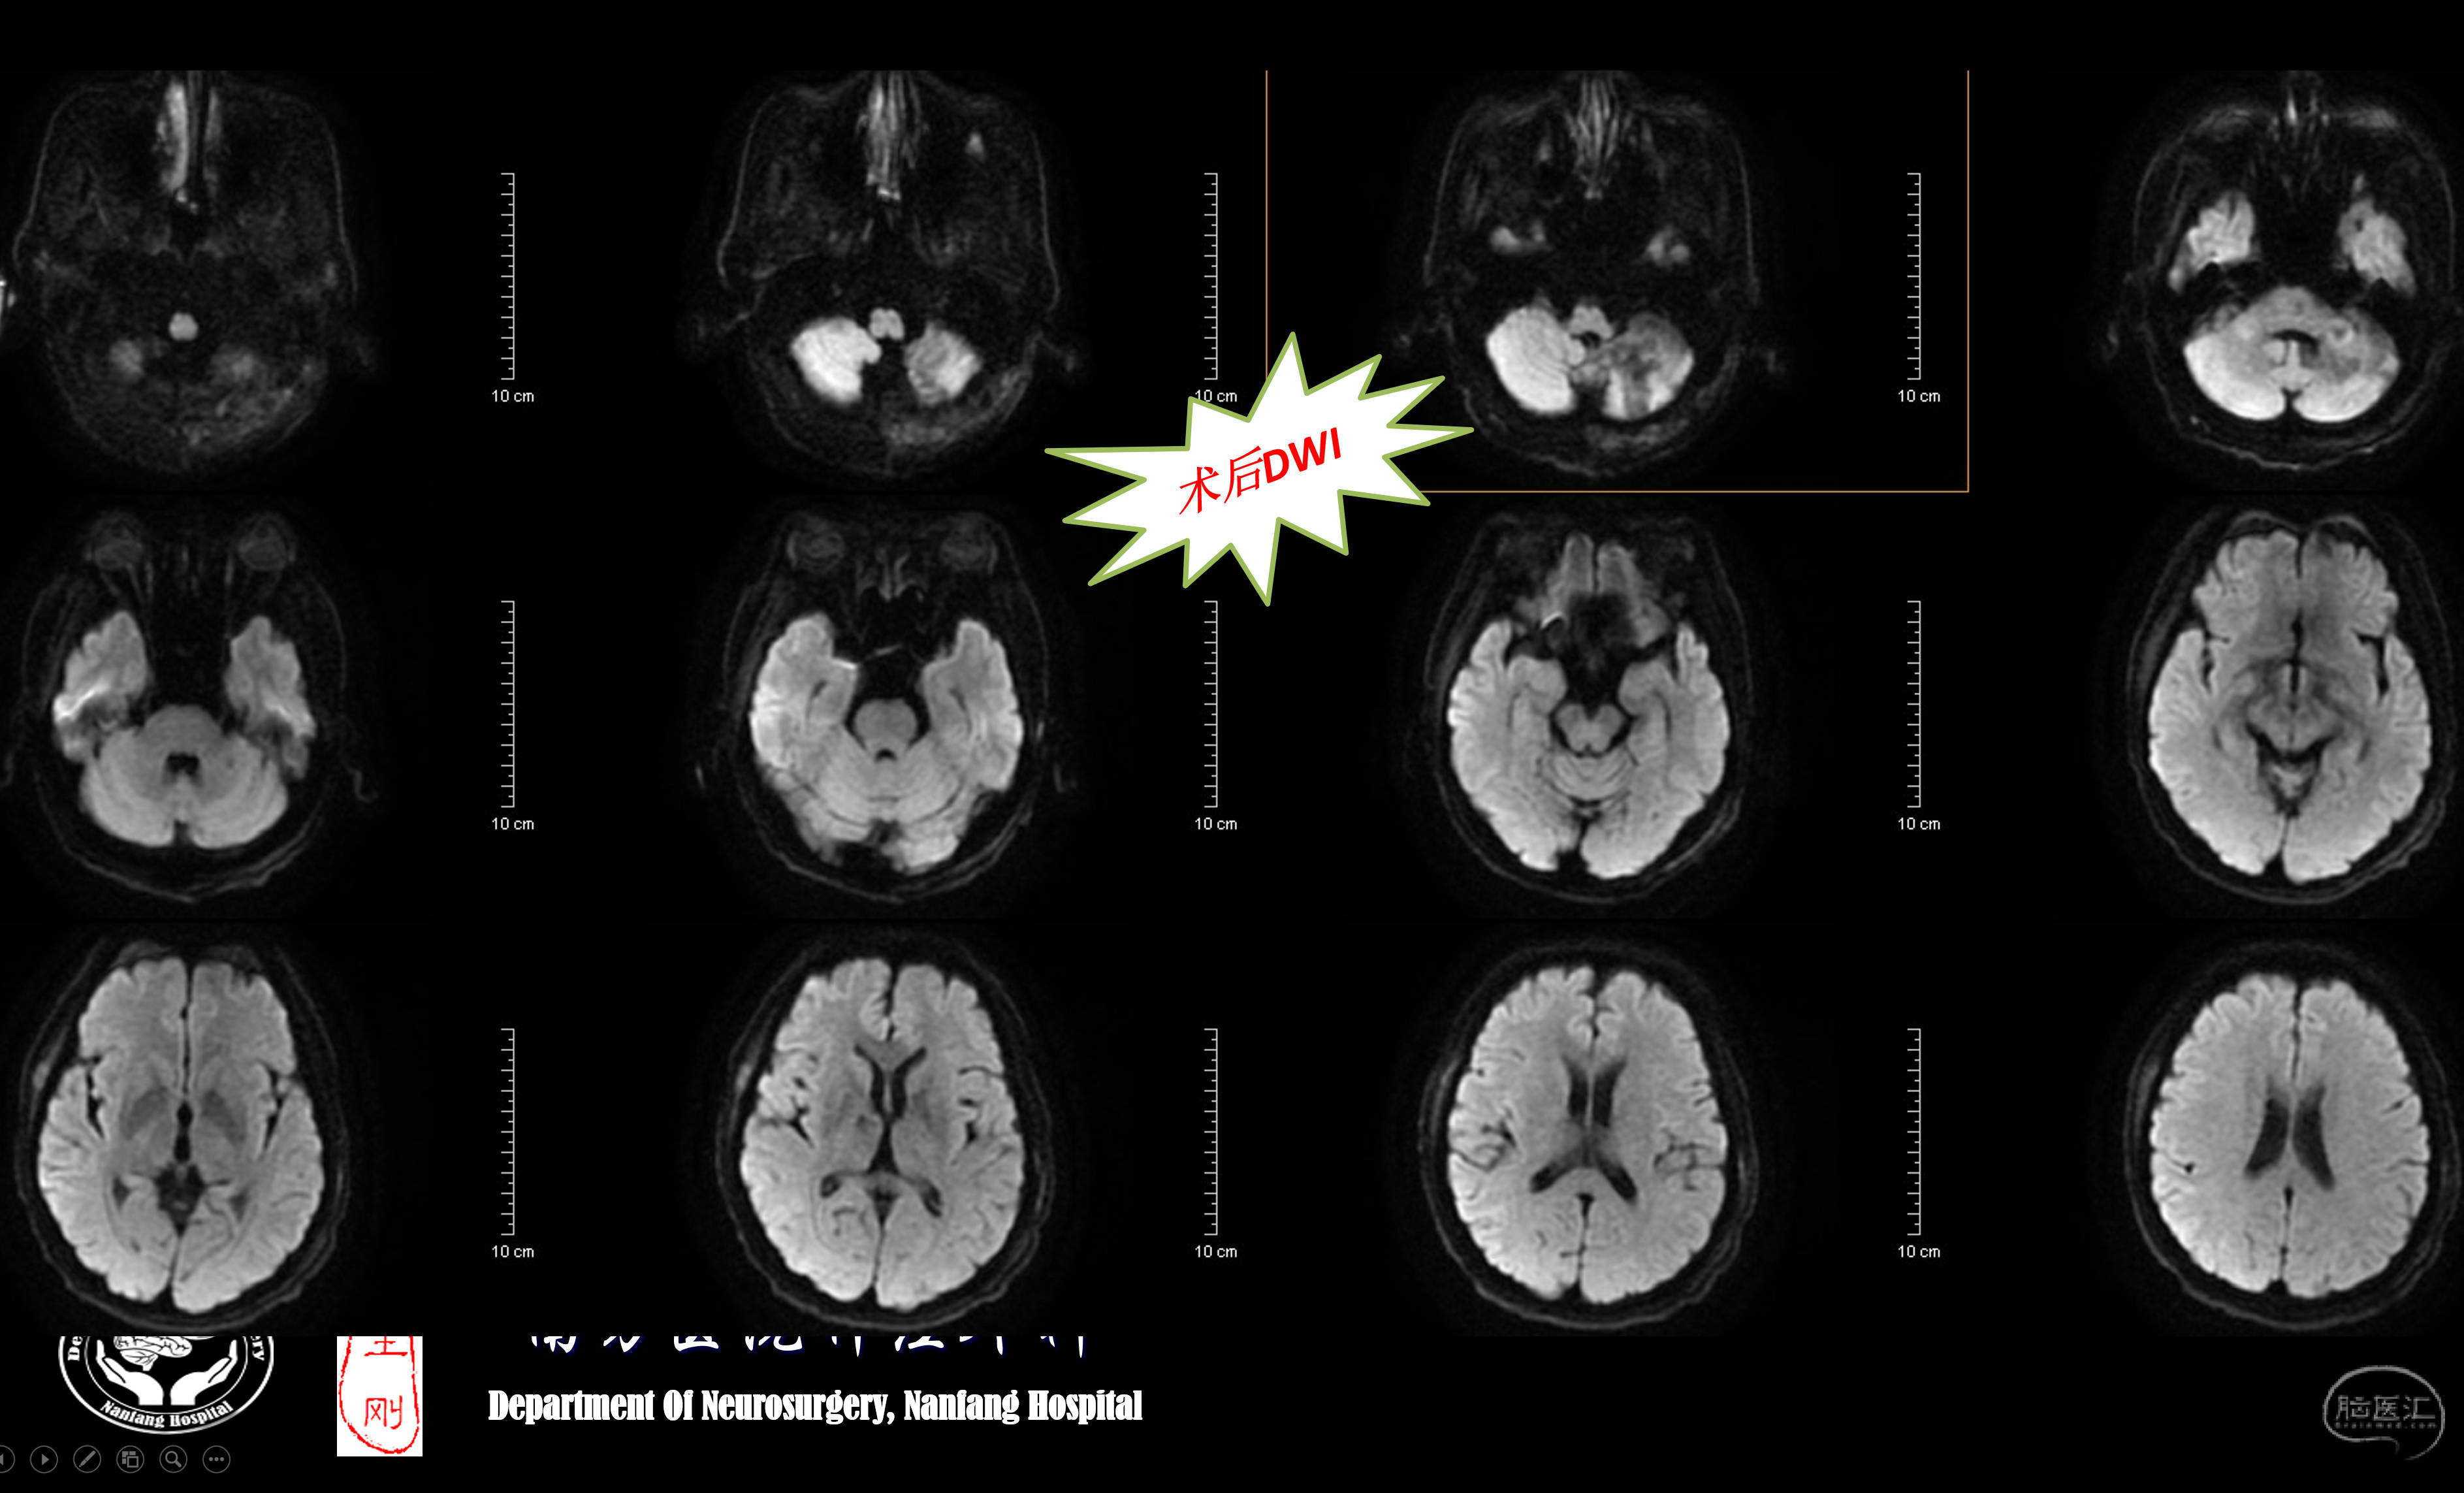

术后DWI未见新发梗塞。